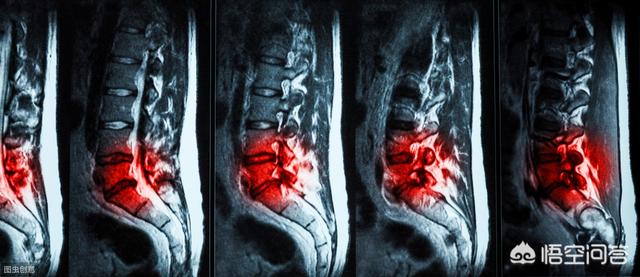

鑵拌倢鍔虫崯鏄寚鑵伴儴鑲岃倝鍙婂叾闄勭潃鐐圭殑绉疮鎬ф崯浼わ紝寮曡捣灞€閮ㄦ參鎬ф棤鑿屾€х値鐥囷紝浠ヨ叞閮ㄥ弽澶嶅彂浣滅殑鐤肩棝锛屽姵绱悗鍔犻噸涓轰富瑕佽〃鐜扮殑鐤剧梾銆俓u003C/p>

鑵拌倢鍔虫崯浼拌澶у鏁颁汉閮戒細閬囧埌锛侀鍏堟垜浠渶瑕佹槑鐧戒粈涔堟槸鑵拌倢鍔虫崯鈥斺€旇叞鑲屽姵鎹熷張绉板姛鑳芥€ц叞鐥涖€佹參鎬т笅鑵版崯浼ゃ€佽叞鑷€鑲岀瓔鑶滅値绛夛紝瀹炰负鑵伴儴鑲岃倝鍙婂叾闄勭潃鐐圭瓔鑶滄垨楠ㄨ啘鐨勬參鎬ф崯浼ゆ€х値鐥囷紝鏄叞鐥涚殑甯歌鍘熷洜涔嬩竴锛屼富瑕佺棁鐘舵槸鑵版垨鑵伴閮ㄨ儉鐥涖€侀吀鐥涳紝鍙嶅鍙戜綔锛岀柤鐥涘彲闅忔皵鍊欏彉鍖栨垨鍔崇疮绋嬪害鑰屽彉鍖栵紝濡傛棩闂村姵绱姞閲嶏紝浼戞伅鍚庡彲鍑忚交鏃惰交鏃堕噸锛屼负涓村簥甯歌鐥咃紝澶氬彂鐥咃紝鍙戠梾鍥犵礌杈冨銆傚叾鏃ョН鏈堢疮锛屽彲浣胯倢绾ょ淮鍙樻€э紝鐢氳€屽皯閲忔挄瑁傦紝褰㈡垚鐦㈢棔銆佺氦缁寸储鏉℃垨绮樿繛锛岄仐鐣欓暱鏈熸參鎬ц叞鑳岀棝銆俓u003C/p>